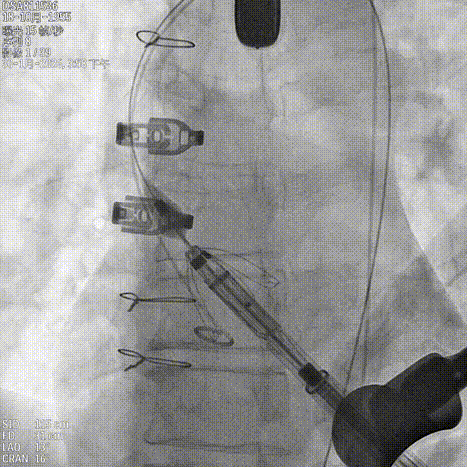

造影确认右窦居中位置

释放定位件尝试入窦

输送系统进行调弯

造影第一次未完全入窦

调整再次入窦

造影确认定位件入窦底